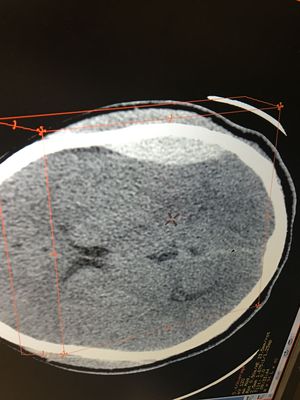

TAC

Hematoma epidural, provocado por traumatismo craneoencefalico

Hospitalinfantil